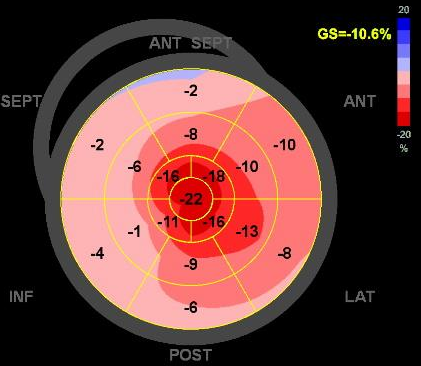

当院での1例を示します。

79才、男性。主訴は労作時息切れ。心臓超音波検査で左室肥大を認め紹介頂きました。採血でNT-pro BNP 2142pg/ml、Troponin T 0.061ng/ml, 心臓超音波検査で左室中隔厚は18.3mm、GLSでapical sparing (図3)を認めました。骨シンチで心臓にGrade 3の集積(図4)を認め、右室中隔からの心筋生検で心アミロイドーシスと診断。現在タファミディス(ビンマック61mg/日)内服中です。